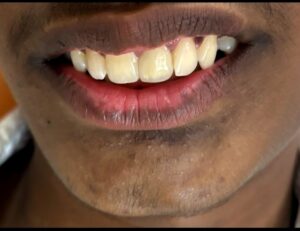

. Smile corrections